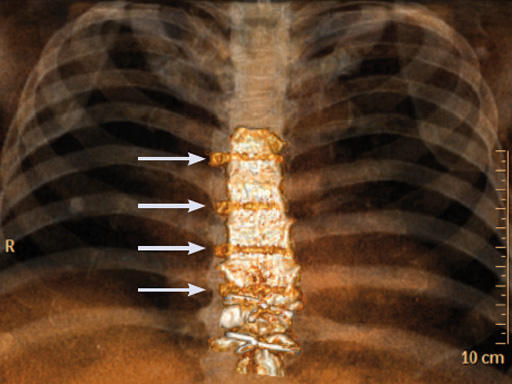

The sternal zipfix system primarily consists of polyetheretherketone (PEEK), biocompatible implants, which are similar to cable ties, and an application instrument. The purpose of this system is to achieve sternal closure following sternotomy by stabilizing the sternum and promoting fusion.

The hybrid sternal closure technique with stainless steel wires and sternal Zipfix has been used in the authors' institution in 50 patients without any instance of sternal instability or dehiscence.

Case 2: A 55-year-old woman, who previously underwent ventricular septal defect closure at 5 and aortic valve reconstruction at 31, required aortic valve replacement due to symptomatic aortic valve insufficiency.

The patient was morbidly obese with a BMI of 45. Due to the high risk for sternal instability and/or deep sternal wound infection, closure was performed using the sternal zipfix system. The zipfix provides quick and reliable stable fixation of the sternum even in patients that are at a higher risk to develop a sternal instability or a deep sternal wound infection.

The postoperative course was uneventful and the patient was discharged on postoperative day 7 with no signs of sternal instability or wound healing problems. At 18 months follow-up the wound had healed completely and the sternum was stable, with no signs of infection.